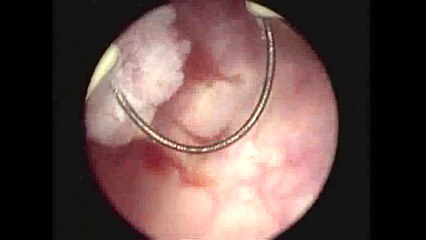

Gary is getting a tumour in his bladder removed, plus his prostate biopsied, under general anaesthetic at Gold Coast University Hospital.